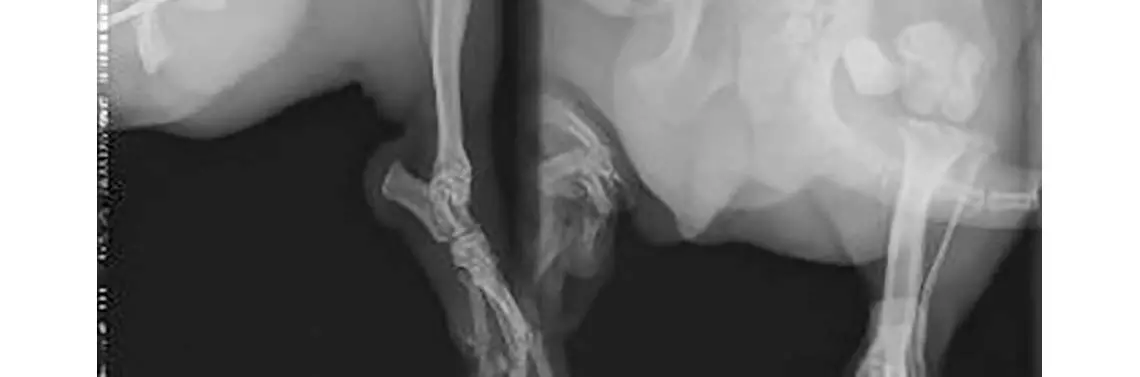

Trzy tygodnie po usunięciu wszczepów pacjent trafił do przychodni autorów w celu konsultacji ortopedycznej. W dniu badania pies wykazywał kulawiznę 4. stopnia, poruszając się na 3 kończynach z luźno wiszącą lewą kończyną miedniczną. Stwierdzono silne zaniki mięśniowe, wyczuwalny przełom złamania oraz krepitację między odłamami. Podczas badania pies wykazywał silne objawy bólowe.

Wykonano zdjęcia RTG w projekcji lewobocznej oraz strzałkowej (fot. 4). Uwidoczniono masywną przebudowę struktur kości udowej z silnym odczynem okostnej odłamu bliższego, cechami osteolizy i znacznego stopnia ścieńczeniem warstwy korowej odłamu dalszego oraz wytworzeniem stawu rzekomego w miejscu przełomu.

RTG boczne i strzałkowe po re-operacji przy użyciu skrzyżowanych gwoździ Kirschnera